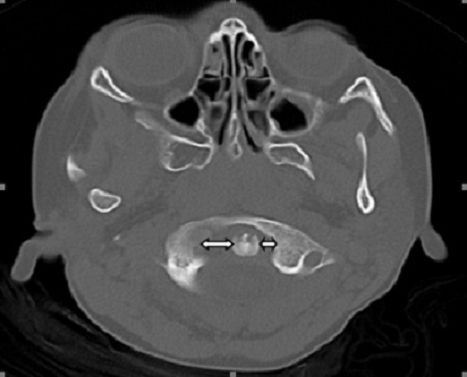

A 7 year-old girl patient was referred from pediatric emergency department (ED) to our emergency department due to cervical pain and neck stiffness. On her physical examination, torticollis was found in the neck. There was no history of trauma. Physical examination showed no focal neurological deficits. On further anamnestic evaluation the patient's parents revealed that she had presented to paediatric ED due to throat and neck pain and put on antibiotics therapy for 5 days. A computed tomography (CT) scan of the patient's neck was performed. A cervical lymphadenopathy associated with atlanto-axial subluxation shadow. The atlas was rotated on one articular process with 3-5 mm anterior displacement, compatible with Type II subluxation. Non-traumatic or inflammatory atlanto-axial subluxation is known as Grisel's syndrome. The subluxation was stabilized with external stabilization (rigid cervical collar). Skeletal muscle relaxants, antibiotics and nonsteroidal anti-inflammatory medications with bed rest were given for further treatment. Early diagnosis of Grisel's syndrome is of crucial importance due to the neurological deficits suc as recurrence or permanent neck deformity. CT, magnetic resonance imaging (MRI) or other imaging tests are required to demonstrate fractures and displaced bone fragments (ie., atlanto-axial subluxation). The primary treatment of early detected Grisel's syndrome is conservative including antibiotic therapy, bed rest, muscle relaxants, external fixation and anti-inflammatory therapy.